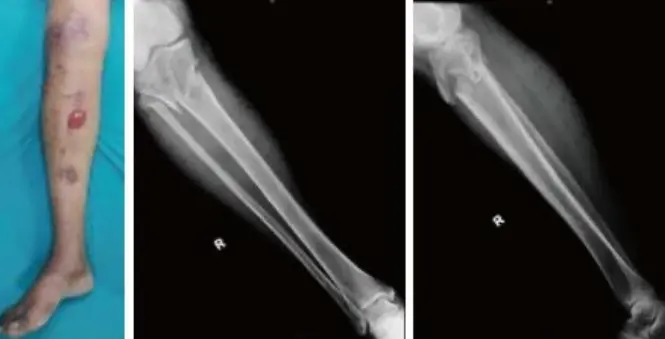

| Compartment Syndrome | Increased pressure within a closed fascial compartment, leading to reduced tissue perfusion, hypoxia, and irreversible muscle and nerve damage. Causes: Fractures (especially tibia/forearm), severe soft tissue trauma, arterial injury, burns, tight casts/dressings, post-ischemic reperfusion swelling, IV fluid extravasation, and bleeding disorders (e.g., hemophilia). High-Risk Notes: Pain may be absent in altered consciousness, children (monitor analgesia response), polytrauma, sedated/epidural cases, or concomitant nerve damage. Open fractures do not always decompress pressure. Gross/Clinical: -tense, shiny leg swelling with blisters in compartment syndrome.Imaging: - Intraoperative fasciotomy | History/Symptoms: Pain out of proportion to the injury (e.g., a “bursting” sensation), which is not relieved by analgesia. Clinical Features (The 5 P’s): - Pain with passive stretch (early, key sign; e.g., ankle dorsiflexion for leg, wrist for forearm). - Paresthesia (early). - Palpable tense swelling (shiny skin, blisters: clear=mild, serosanguinous=severe, bloody=worst; dusky/pallor skin). - Pallor, Paralysis, Pulselessness (late, ominous signs; pulses often palpable until late). Investigations: Primarily a clinical diagnosis (high suspicion key). Compartment pressure measurement can confirm: absolute pressure >30 mmHg or Delta Pressure (Diastolic BP - Compartment P) ≤ 25 mmHg. | Initial: ABCs, supplemental oxygen. Remove all circumferential dressings, casts (bivalve to skin), and splints. Elevate the limb to heart level (not above; higher reduces inflow). Correct any hypotension. Surgical: Urgent Fasciotomy if no response within 1h or confirmed pressure (prophylactic in high-risk like major osteotomy). Release all compartments/skin with long incisions; debride necrotic muscle via 4C’s (early: pink/red, soft, contracts/bleeds on pinch; late: dark, firm, no response); preserve neurovascular. Wound open (bulky dressing/splint, VAC, or boot-lace gradual closure); repeated inspections x48h; coverage in 3-5 days (skin graft usual; flap if nerves/vessels/bone exposed). | Cellulitis, Deep Vein Thrombosis (DVT), Arterial occlusion, Severe soft tissue injury without compartment syndrome; equivocal cases in polytrauma. | Complications: Volkmann’s ischemic contracture (permanent deformity, weakness, sensory loss, chronic pain). Contraindications (Fasciotomy): Confirmed >48h (irreversible damage, high infection risk from dead tissue); crush injuries with already necrotic muscle. |

| Open Fracture | A fracture with a breach in the overlying skin and soft tissues, creating communication with the external environment. All open fractures are considered contaminated (even small punctures; aka compound fracture). Causes: Can result from high-energy trauma (RTAs, falls, firearms; signs: degloving, crush syndrome, bone loss, segmental) or low-energy trauma. Contamination risk higher with farm/soil injuries, bites, delayed presentation (>12h), fecal/oral/soil/water exposure. Mechanism: Low/high velocity missiles (cavitation >300 m/s); in-out (cleaner) vs. out-in (dirtier). Gross/Clinical: ![]() | History: Mechanism of injury (energy, time, place, type/impact method), consciousness, wound size/bleeding amount, other injuries (often missed), tetanus status. Assessment: ATLS protocol (ABCDE) first (treat patient, not fracture; exclude shock/brain injury, monitor vitals; viscera exam: ribs=lungs/liver/spleen, pelvis=bladder/urethra). Examine wound (look/feel/move carefully post-splint), check distal neurovascular status, compartment syndrome. Photograph/remove gross contamination; cover with saline dressing. Classification (Gustilo-Anderson): - Type I: <1 cm wound, clean, minimal soft tissue. - Type II: >1 cm wound, moderate soft tissue (no stripping). - Type IIIA: Extensive soft tissue damage, but adequate bone coverage. - Type IIIB: Extensive soft tissue loss with periosteal stripping; bone exposed, requires flap coverage. - Type IIIC: Any open fracture with an arterial injury requiring repair. | Initial (ER): ATLS first. Cover wound with sterile saline-soaked dressing, splint limb, IV fluids (request blood if needed); traction if no distal pulse/deformity. Prophylaxis: Tetanus prophylaxis/serum and broad-spectrum IV antibiotics immediately (culture tissue/blood); clean major contamination. Surgical: Urgent debridement/irrigation within 6-12h (“Dilution is the solution to pollution”; pulse-irrigate 3-6-9L saline; excise non-viable tissue/foreign material, trim skin edges, remove dead muscle/detached bone, preserve N/V). Stabilization: external fixator (preferred severe; replace with cast post-infection); internal if clean/minimal. Wound closure delayed (primary if small/clean; secondary if contaminated/large). Early soft tissue cover. | The diagnosis is typically obvious. Key: Classify severity; identify associated injuries like compartment syndrome, vascular damage, or high-energy signs (e.g., crush). Differentials for contamination: Primary (field debris) vs. secondary (post-fixation if poor debridement). | Complications: Infection (cellulitis, osteomyelitis, chronic with sequestra/drainage, gas gangrene), tetanus; higher with delay/exposure/bites. - embolisms fat, thrombi others.. Case Insight: Unconscious patient (e.g., open tibia post-RTA): ABCDE/cervical collar, distal pulses/traction, admit for debridement; ankle fall: Splint post-ABC, assess neurovascular. |